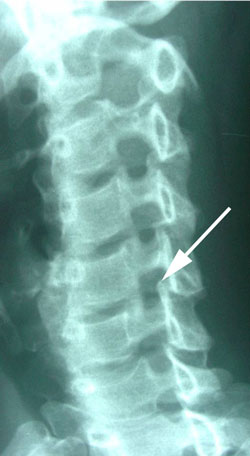

cervical spine instability

Figure 2 shows the neck in a forward flexed position with the chin on the chest. Note at the arrow that the vertebra that was positioned back on the vertebra below in Figure 1 is now moved forward to a normal position. This again shows the instability of the spine due to tearing and sprain of the disc between the vertebrae. This is an example of marked instability.

extension instability of cervical spine

Figure 3 is an xray taken with the patient looking up to the ceiling, or placing the neck into extension motion. Note that the vertebra at the arrow has moved backward on the vertebra below, again demonstrating instability of the intervertebral disc. Compare this vertebra position at the arrow to the same position shown in Figure 2 in which the vertebrae are in normal alignment.

cervical spine minor stenosis

Figure 4 is called an oblique x-ray of the neck and this view allows the reader to look into the nerve openings and note any diminished size of one opening to other openings in the cervical spine. In this case, at the arrow, note the narrow front to back size of that opening compared to adjacent levels. This noted level is the level of backward position of one vertebra on the one below. This narrowing compressed the nerve passing through it and sometimes this narrowing is termed minor stenosis.